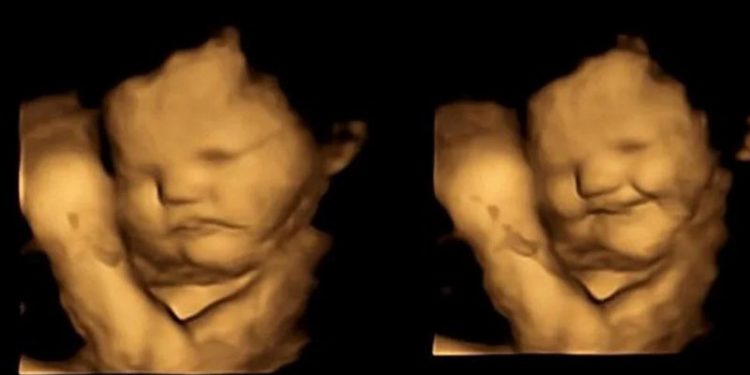

Yeni bir araştırma, bebeklerin daha anne karnındayken farklı tatlara tepki vermeye başladığını gösterdi. Durham Üniversitesi’nden araştırmacılar, 100 hamile kadın üzerinde yaptıkları çalışmada, dört boyutlu ultrasonla anneleri sebze yediğinde bebeklerin verdikleri tepkileri ölçtü.

Bebekler, anneleri havuç yedikten kısa süre sonra gülümserken, anneleri lahanayı tercih ettiğinde yüzlerini buruşturdu. Bulgular, hamile kadınların yediklerinin doğumdan sonra bebeklerinin tat tercihlerini etkileyebileceğini gösteriyor. Araştırmacılara göre, sonuçların sağlıklı beslenme alışkanlıkları oluşturmada etkileri olabilir.

Yaşları 18 ile 40 arasında değişen 100 hamile kadın, hamileliklerinin 32’nci haftası ile 36’ncı haftası arasında dört boyutlu ultrasonla takip edildi. Kadınlara her ultrason taramasından 20 dakika önce 400 mg havuç ve 400 mg lahana kapsülü verildi; bu esnada başka bir şey yiyip içmemeleri istendi. Kontrol grubundaki bazı kadınlara ise her iki kapsül de verilmedi. Sonuçlar, düşük miktarda havuç ve lahananın anne karnındaki bebeklerin tepki vermesi için yeterli olabileceğini gösterdi.

Kadınlar havuç yediğinde fetüsler gülümserken, laha kapsülü fetüslerin yüzlerini buruşturmalarına yol açtı. Araştırmayı yapan ekibin başındaki isim Beyza Üstün, “Henüz doğmamış bebeklerin lahana ve havuç tatlarına verdiği tepkileri görmek ve bunları ebeveynleriyle paylaşmak inanılmazdı” dedi.